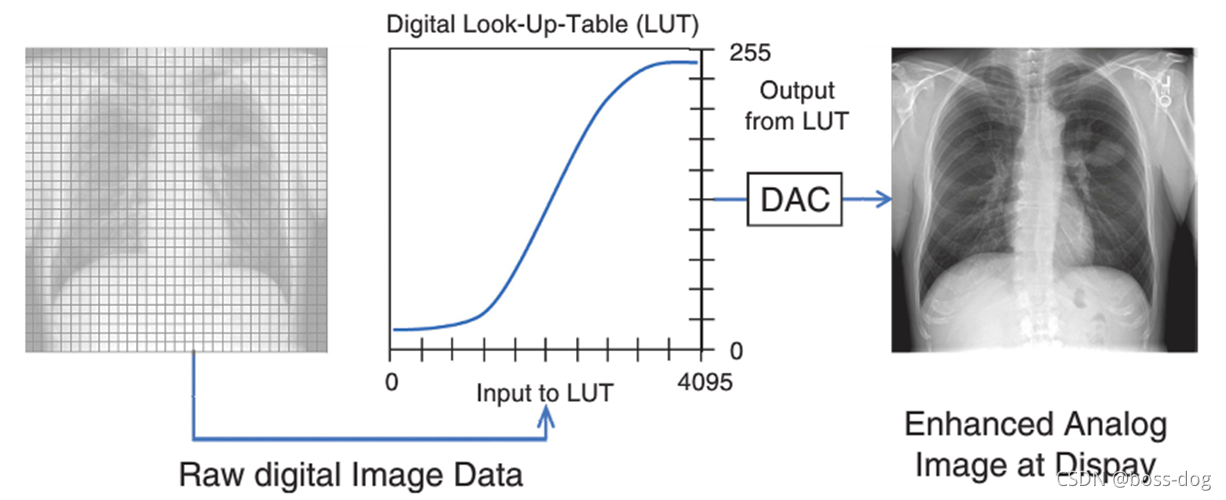

Display contrast(显示器地对比度)

医学图片中希望把最黑的、最亮的、中间的能够完美地显示出来。

上图中如何将灰度转换为显示器上的实际密度:

窗口宽度(Window width,W)

window level(L)

饱和至黑色:L - W/2

饱和至白色:L + W/2

1.检测器信号范围是0-4000计数/像素。

2.PC显示器相对亮度0-2000。

3.图像具有有用区域的信号范围为500-3000计数/像素。

像CT的话,窗口很宽,从负一千到正一千,如果全部显示出来的话,人眼不一定能够把那些细节检测出来看出来,所以针对CT,可以调整图像。